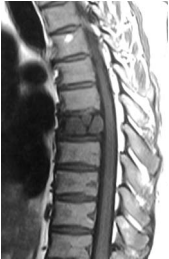

This 43-year-old Caucasian male first presented to a doctor with a complaint of mild thoracic back pain with radiation round the left chest. He had no neurological deficits. X Rays done showed any abnormalities. MRI showed a post contract enhancement in the left half of the T7 vertebra. A CAT guided needle biopsy done was not conclusive. He was then referred for further management, about 5 months after he noticed thoracic backache. Pain was described as a discomfort, occasionally sharp and radiating around the mid left chest. He had no neurological deficits and no myelopathy.

A repeat MRI showed post contrast enhancement of most of T7 vertebra. There was no cord compression.